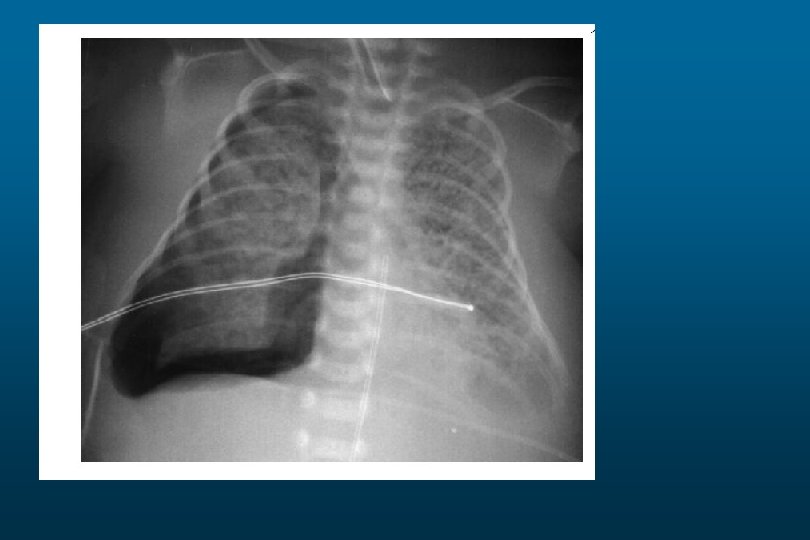

Right sided atelectasis

he right hemithorax is opaque There is a shift of the heart and trachea

he right hemithorax is opaque There is a shift of the heart and trachea away from the side ofo pacification This is characteristic of apleural effusion